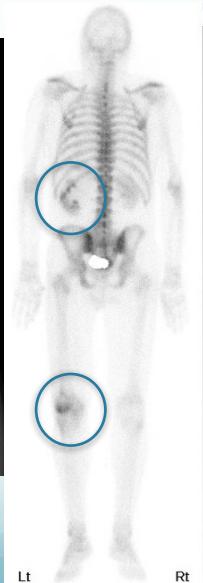

- Bone scan

Source: https://radiopaedia.org